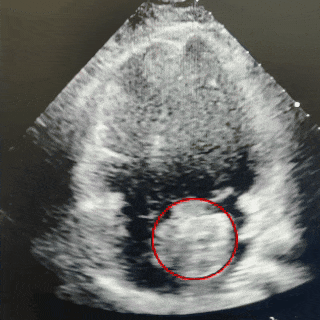

主动脉短轴切面

封堵器锁定成型后,超声下多切面确认封堵器盘面贴合,稳定夹持缺损。